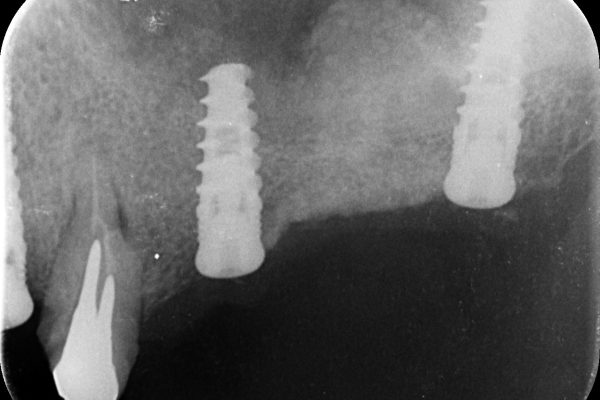

Some clinical cases with kit A (Indication less than 4 mm of sub-sinus bone),